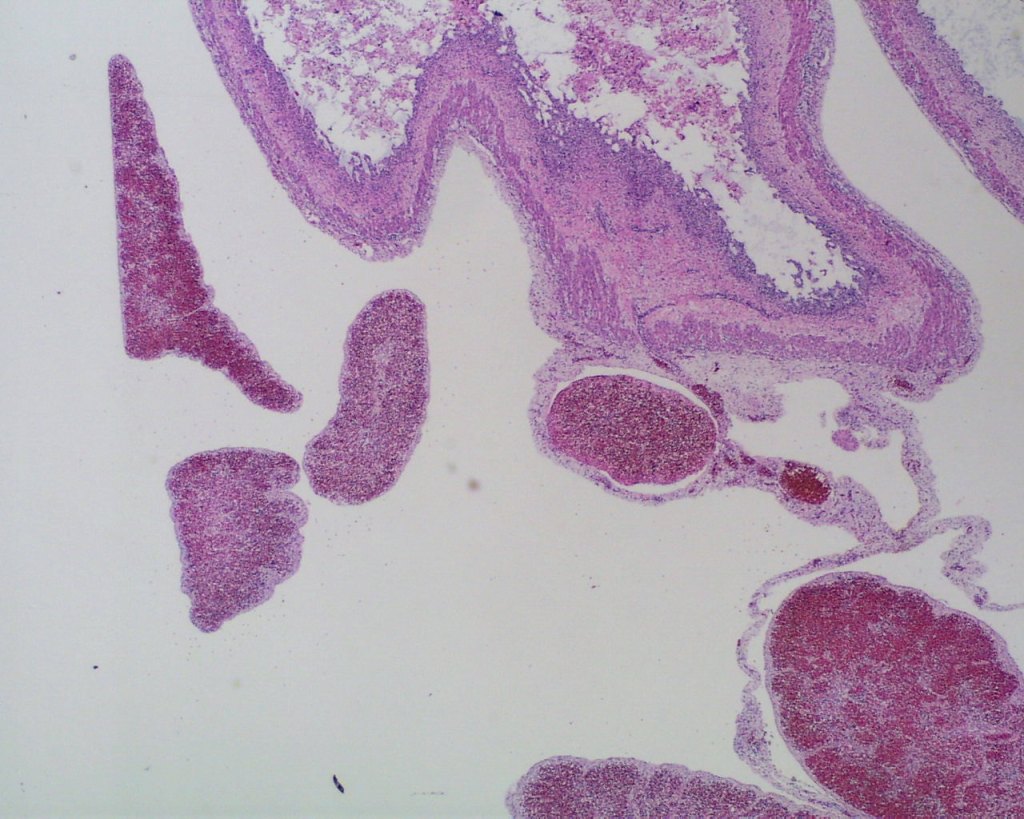

Fig1 b: Multiple spleens can be seen microscopically in this 19 weeks of gestation infant with polysplenia syndrome with situs inversus and complex cardiac malformations. The infant had 12-24 hours of postmortem retention.

Lymphoid tissue: The normal fetal spleen demonstrates a cuff of predominantly T lymphocytes around the arterioles (Fig 3a, b).

Fig 3b: The lymphocyte cuffs can be seen around the spiral arteries in this 32 weeks of gestation infant with acute asphyxia and 6 hours of intrauterine postmortem retention. (4x, H&E)